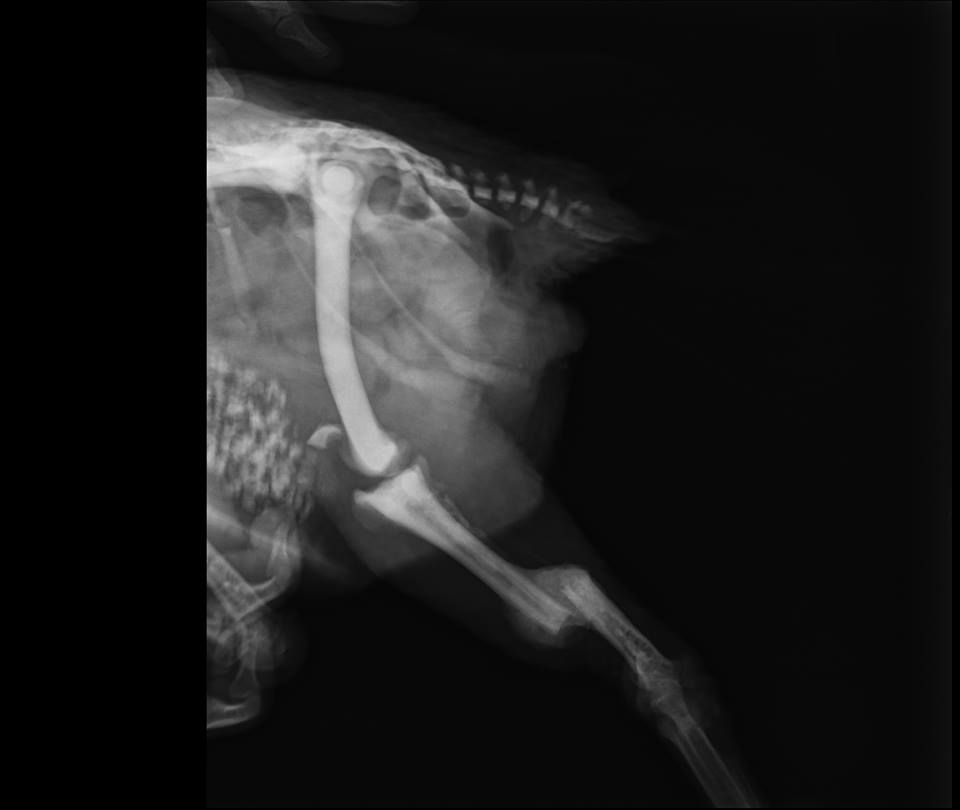

Rosehip (Csipke in Hungarian, she is the left one on the picture) came from a family farm where we found her with a broken leg. She received a life-saving surgery where a fantastic vet mended her leg. She is able to walk now again and she is truly the soul (and sound ;) ) of our home... :D

Juoda (Miss Black :D ) also came with a broken leg, but her leg was beyond repair. It was broken for a long time and it healed wrongly. She is able to walk but she is disabled for life... However, she has a strong and adorable spirit! We love her around! She is much (!) calmer and wiser then Csipke :P

Csipke's leg before

AND after the Operation

The state of Juoda's leg

(wrongly healed